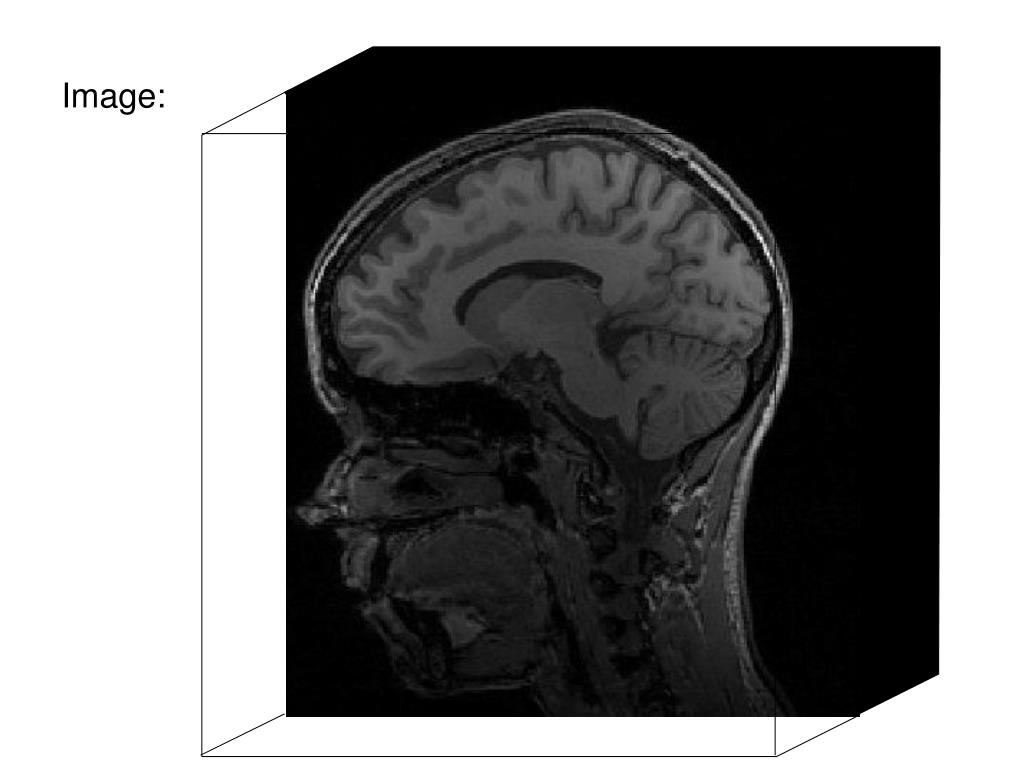

6. Image:

31. Image: